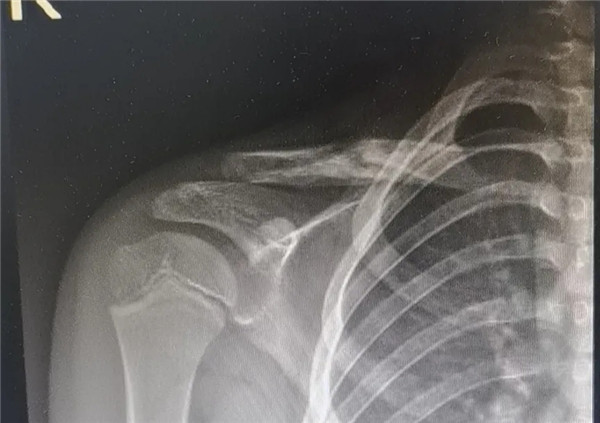

6月3日,在征得家屬同意,洋洋的身體符合手術(shù)指征后,洋洋接受了右鎖骨骨折切開(kāi)復(fù)位內(nèi)固定術(shù),手術(shù)由應(yīng)文世主任主刀。術(shù)中可見(jiàn)右鎖骨呈粉碎性骨折,骨折端移位明顯。一個(gè)小時(shí)后,手術(shù)順利結(jié)束。術(shù)后,洋洋恢復(fù)良好,6月9日順利出院。一個(gè)月后,在來(lái)復(fù)查時(shí),洋洋的媽媽帶來(lái)了一面錦旗送予應(yīng)文世主任及手外科周小君副主任,以感謝他們的高超技術(shù)及優(yōu)質(zhì)服務(wù)。

復(fù)位后